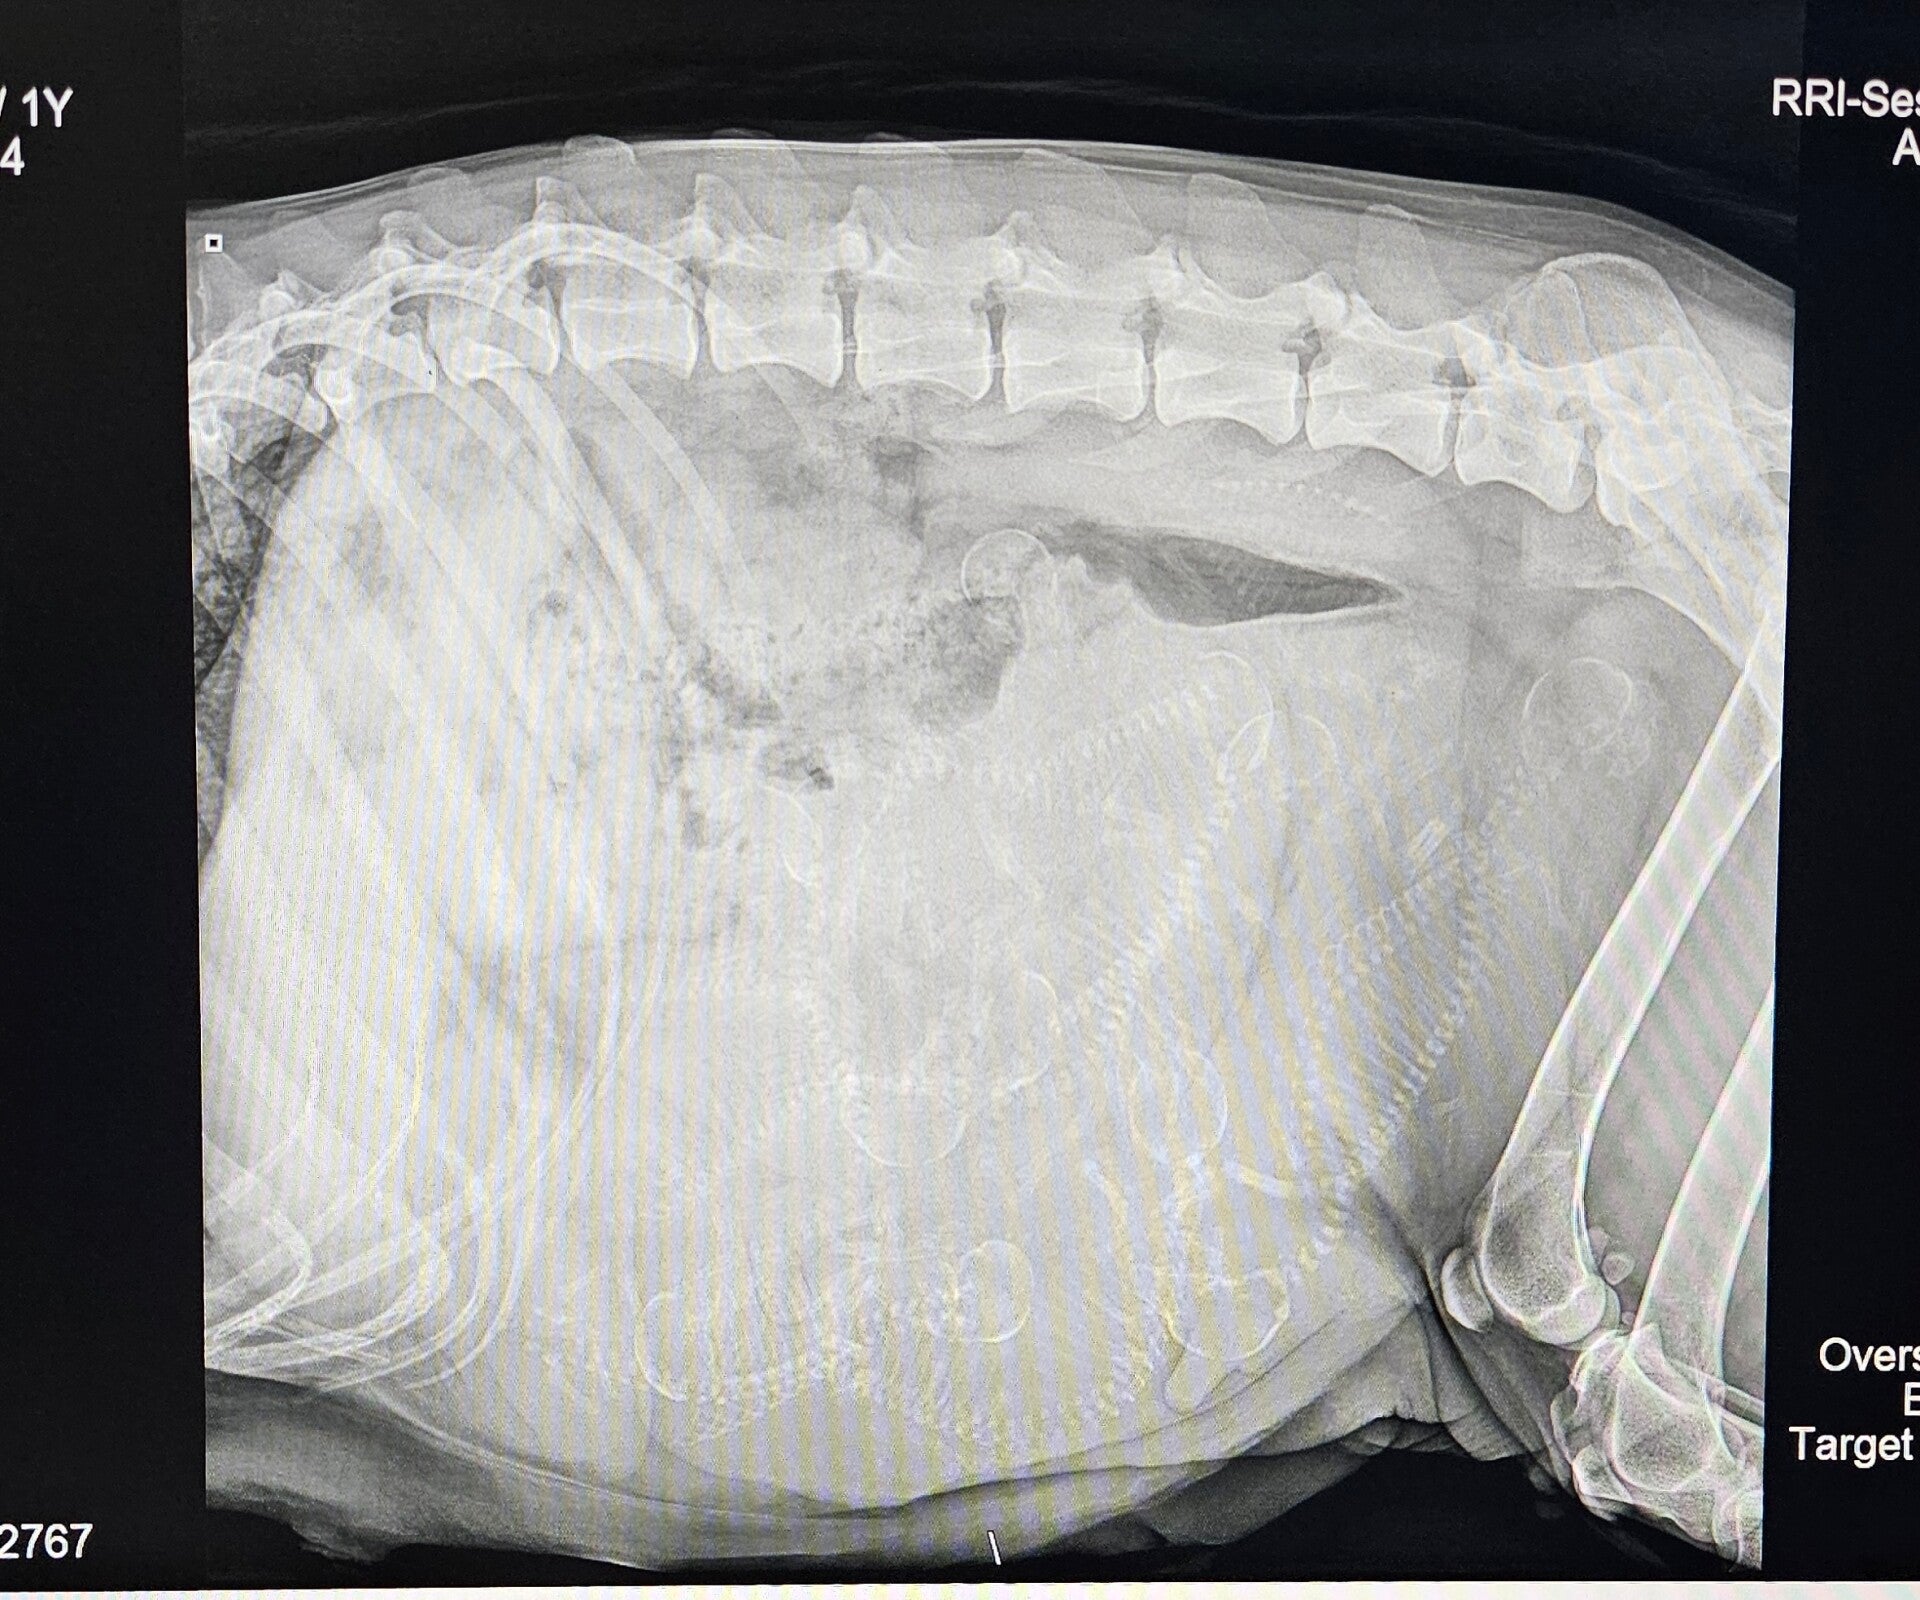

Gabbi's 53 Day Prenatal X-ray

Gabbi had her puppy count X-ray today. 5-7 developing puppies is now more like 12! It's going to be a big litter. We have her due date at Feb 21st, but I'll be surprised if she doesn't go early. We are so excited to welcome a dozen little ones to the world!

12 possible skulls and spines